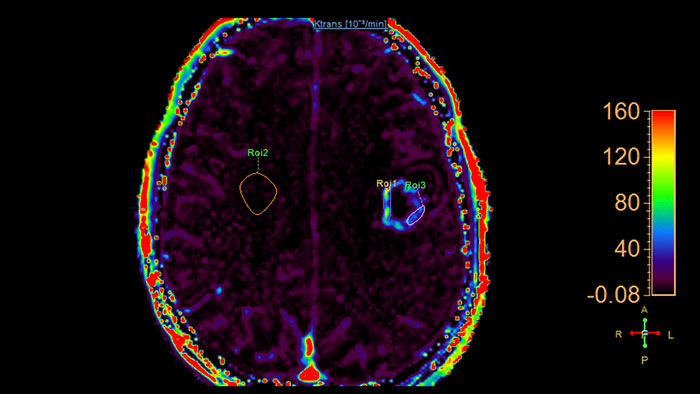

Permeability

MR Permeability

Lesion characterization by reviewing vascular leakage

Designed to visualize T1 weighted DCE 3D datasets and assist in analyzing the tissue response.

• Calculates parametric maps such as Ktrans, Kep, ve and vf.

• The application has been validated for prostate and brain cancer.